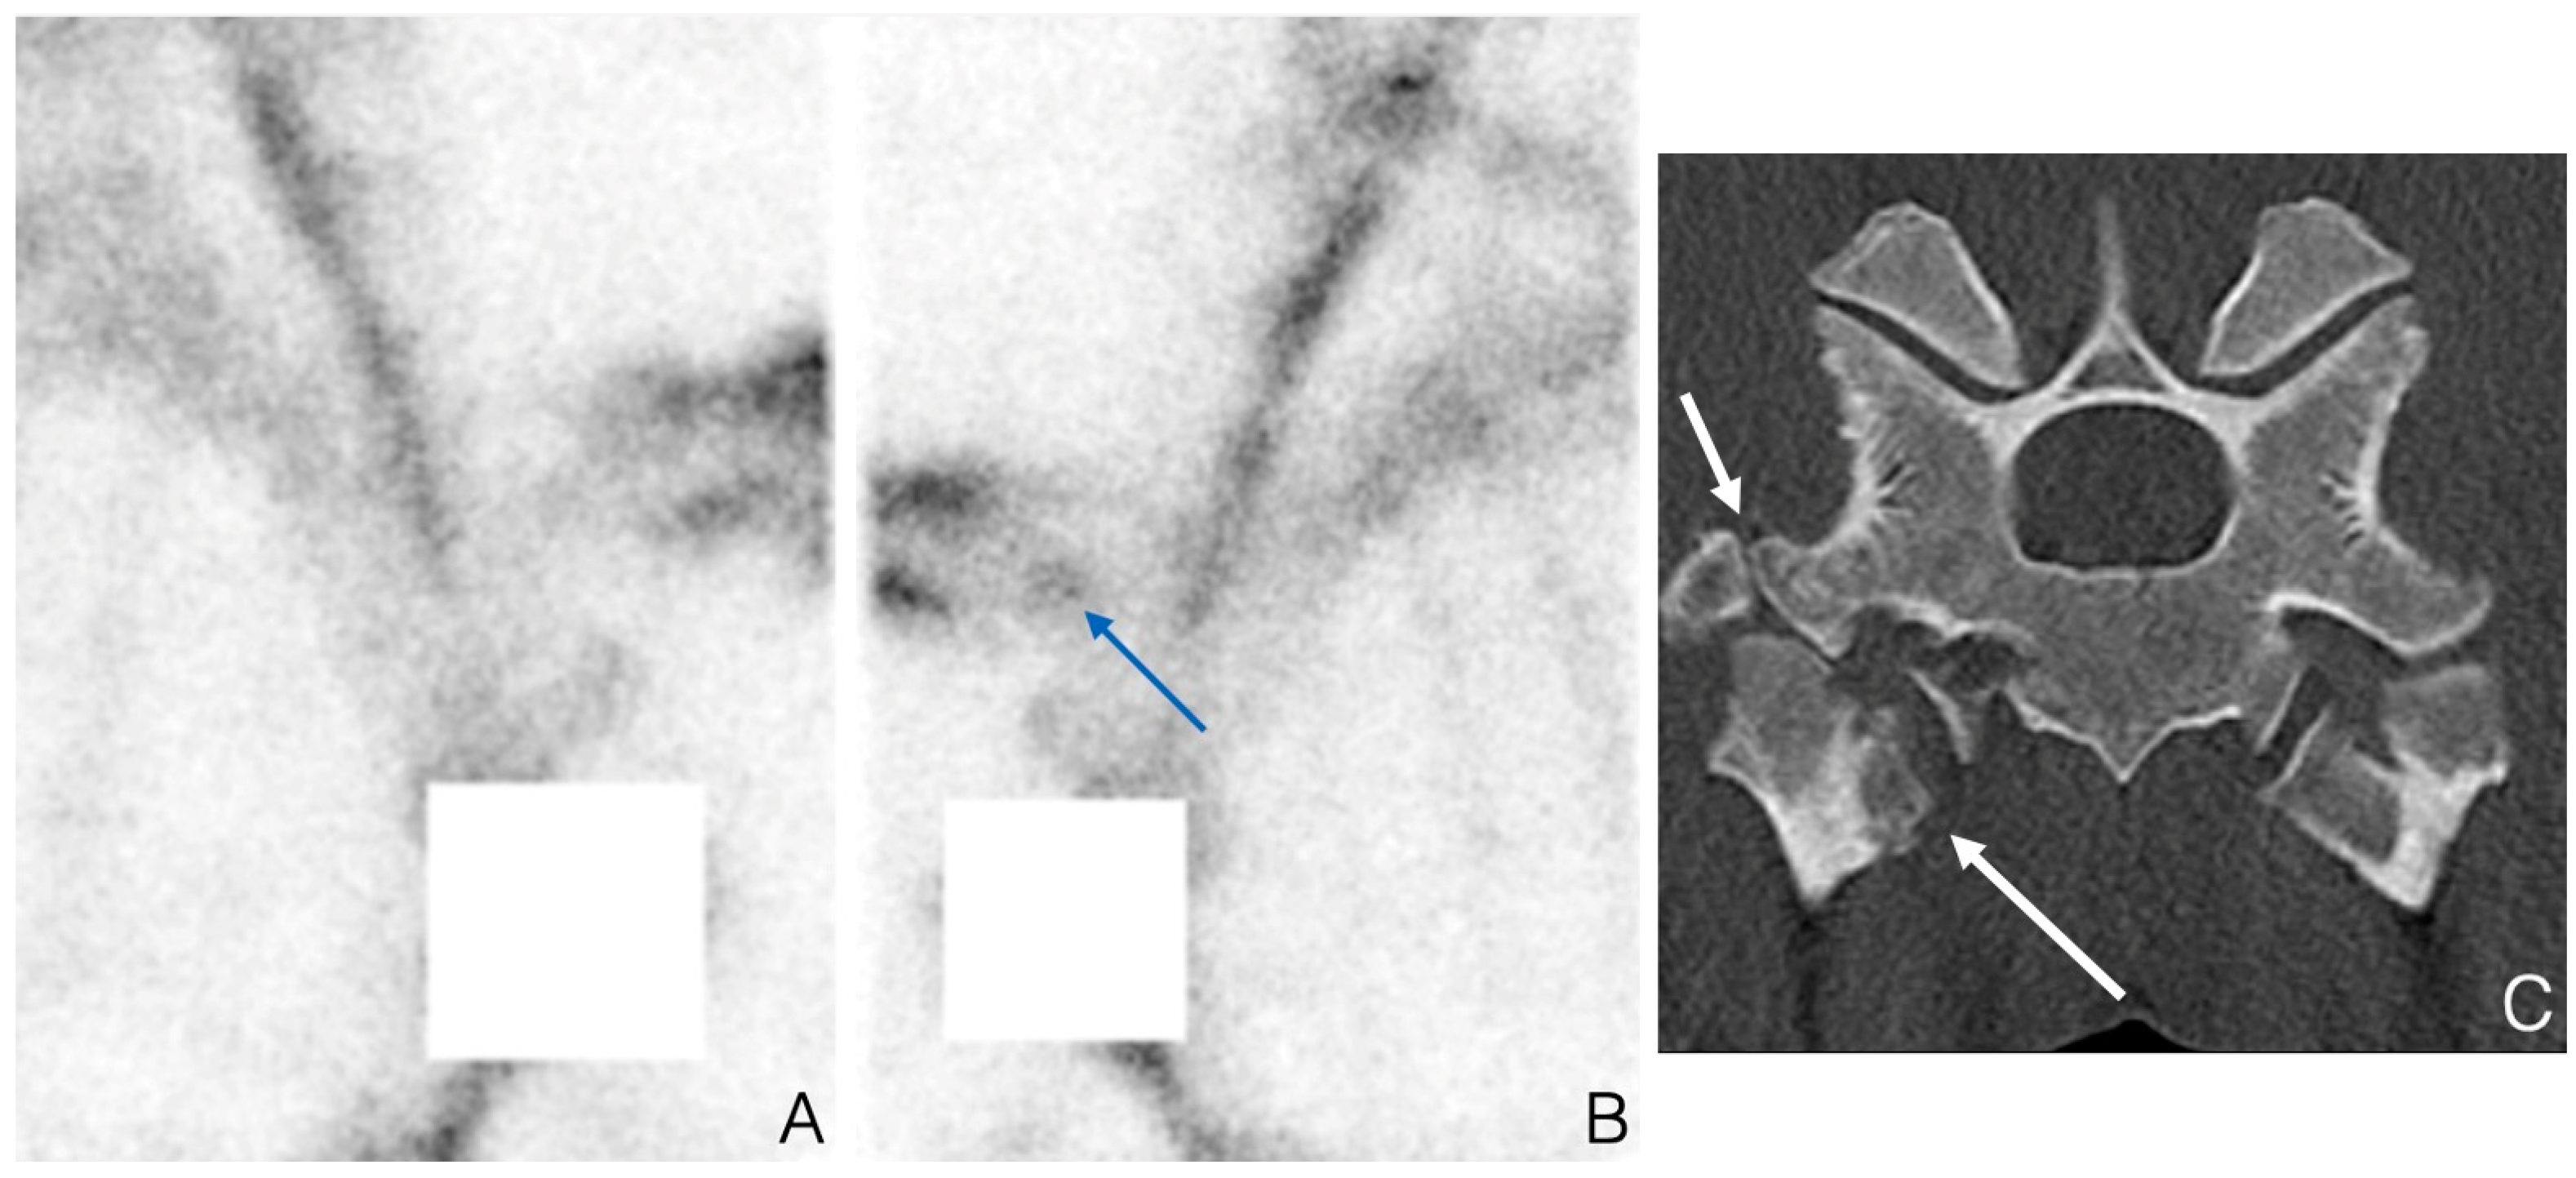

3.2. Scintigraphy Combined with CT and MRI

3.3. Scintigraphy and Longitudinal Follow-Up